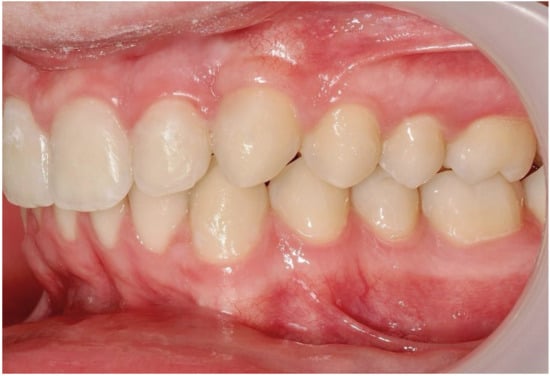

3.2. Representative Clinical Case

A 13-year-old male patient presented with Class II Division 2 malocclusion, a bilateral Class II sagittal relationship, and retroclined incisors. Cone-beam computed tomography revealed a palatally impacted maxillary left canine (tooth 23), with its cusp located palatally to the apical half of the left lateral incisor. The root exhibited significant apical curvature, extending toward the floor of the maxillary sinus (Figure 12 and Figure 13), making spontaneous eruption unlikely.

Figure 12.

Initial intraoral lateral photo.